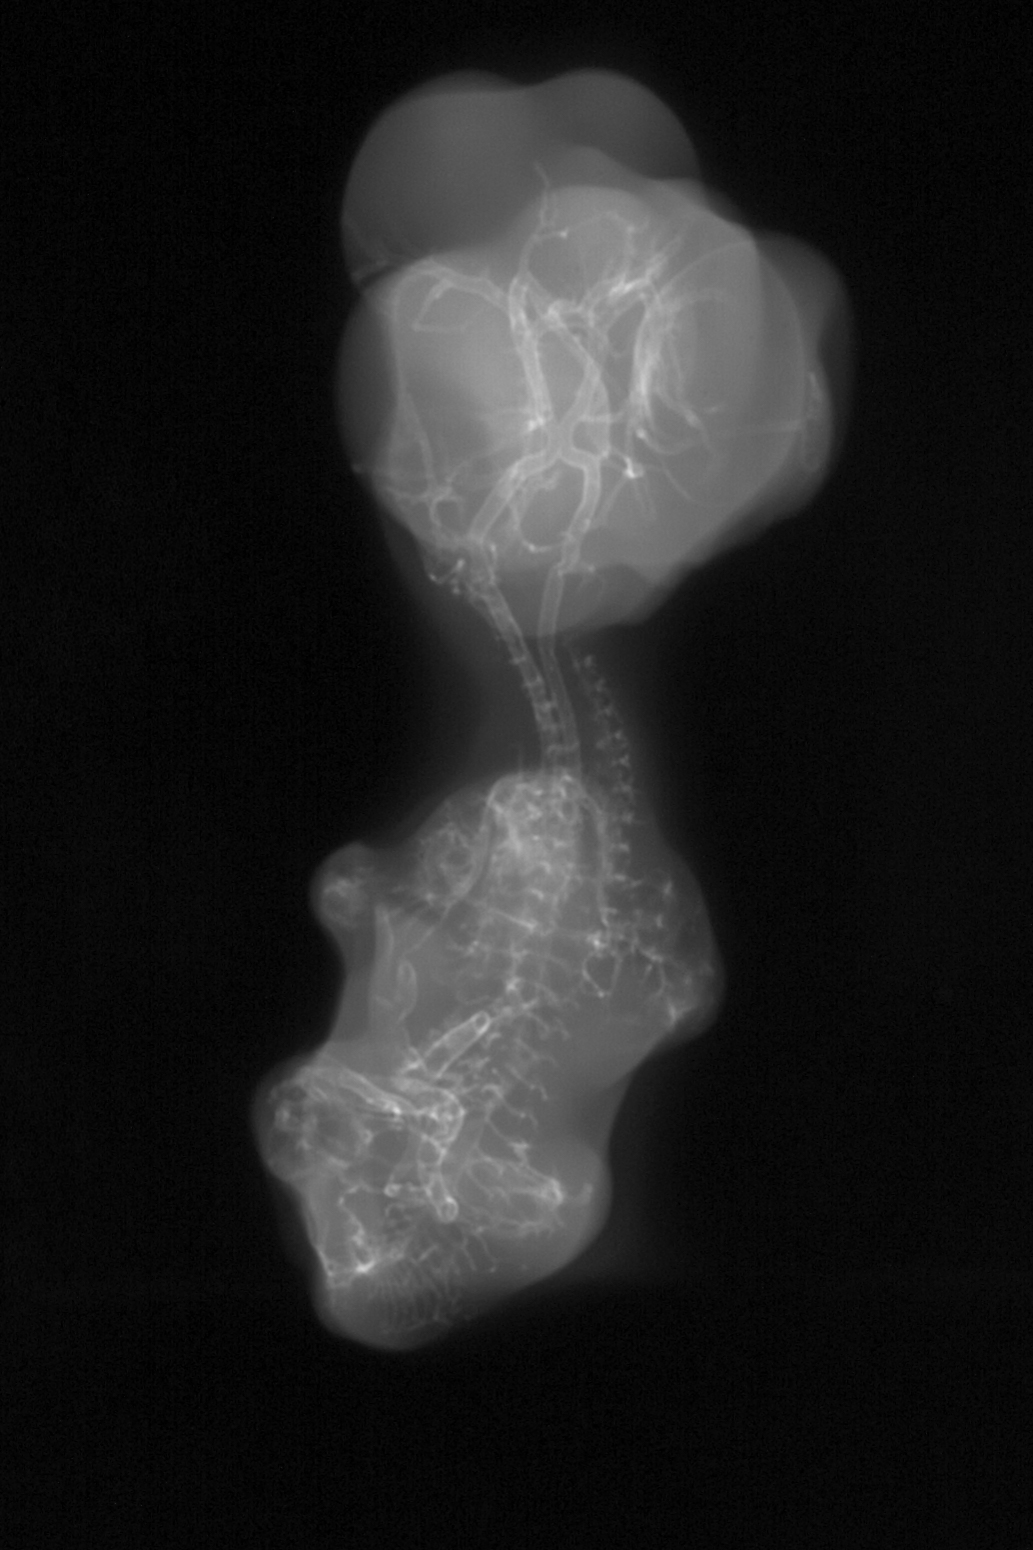

Hamburger-Hamilton (HH) Stage 29 (approx. 6 - 6.5 days)

X-Ray Micrographs